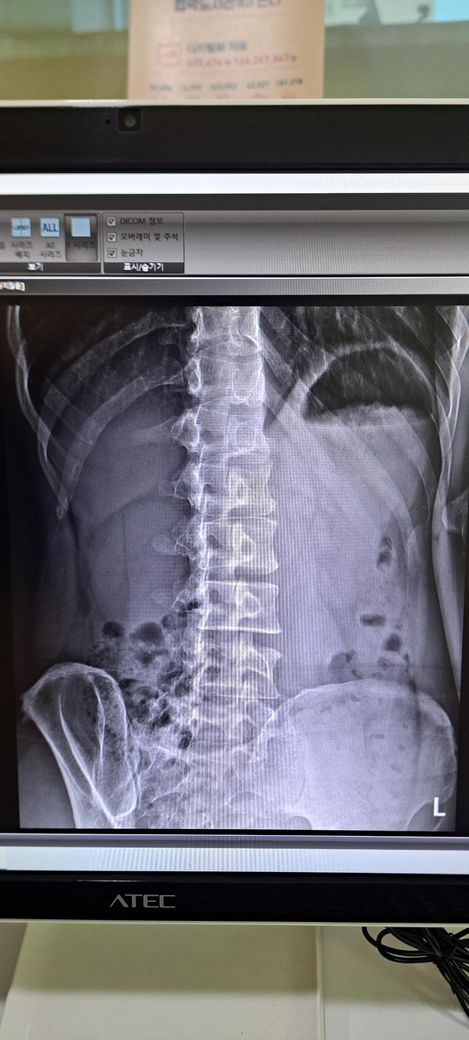

x ray 촬영한 영상인데 골반 틀어짐 및 전방경사 심각한가요? 골반 틀어짐은 어느 쪽을 교정해야 하며 골반 틀어짐 및 전방경사 교정 방법을 알려주시면 감사하겠습니다 .

사진상으로 골반 좌우 비대칭은 약간 의심되지만, 단순 X-ray만으로 "심각한 틀어짐"이라 단정하긴 어렵습니다.

일단 골반 같은 경우 좌우 대칭이 다르며 약간의 전방 경사 및 틀어짐이 있는 것으로 보입니다.

정면 사진상 골반의 좌우높이 차이가 관찰되며, 이는 대퇴골의 위치변화와 연관되어 보입니다. 측면 사진에서 요추의 곡선이 다소 꺾여 있는 양상이 보여 골반 전방경사 가능성이 큽니다. 정면 영상에서 척추가 일직선이 아니라 완만한 S자 형태로 휘어있는 측만 소견이 보입니다. 심각한 수준은 아니나 지속적인 관리가 필요한 상태입니다. 측면 사진상 경추의 커브를 보면 일자목 상태입니다. 골반이 높은쪽의 근육은 이완시키고, 낮은쪽과 약해진 둔근, 복근을 강화하는 운동이 필요합니다. 전방경사 완화를 위해 장요근 스트레칭과 프랭크 같은 코어 운동이 효과적입니다. 흉쇄유돌근 스트레칭과 더불어 등 근육을 강화하여 어깨를 펴는것이 급선무입니다.

골반 틀어짐을 보면 오른쪽 골바 날개가 왼쪽보다 높이 위치한걸 볼 수 있습니다. 하지만 이 사진만으로 판단하기보다는 발끝까지 찍은 사진을 보고 왜 오른쪽 골반이 더 위로 높아져있는지를 판단해야 원인과 해결법을 판단할 수 있겠습니다.

척추측만은 의미있는 정도가 아닙니다. 저희가 20도 이상을 증상을 유발할 수 있는 측만으로 보는데 그만큼 측만이 확인되지 않습니다.